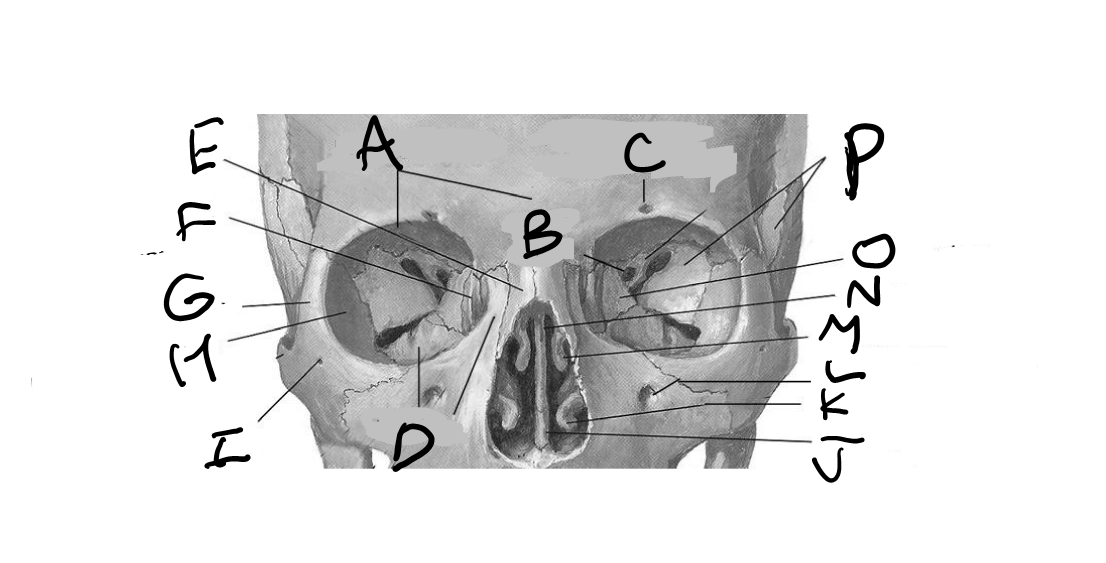

C - Optic nerve *this is the lesser wing of the sphenoid bone with the optic canal that contains the optic nerve and ophthalmic artery*

What is A?

Iris

Perpendicular plate of the ethmoid bone

Medial rectus

What is E?

Nasal bone

What is C?

Inferior rectus

Supraorbital foramen/notch

What is D?

Maxilla

What is G?

Zygomatic frontal process

What is I?

Zygomaticofacial foramen

What is H?

Zygomatic orbital surface

What is K?

Inferior nasal concha

What is J?

Vomer

What is O?

Orbital plate of the ethmoid bone

Frontal bone

What is P?

Greater wing of sphenoid